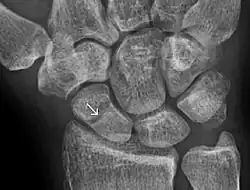

Radiolucency around a 12 days old scaphoid fracture that was initially barely visible.[13]

Scaphoid fractures are often diagnosed using plain radiographs and multiple views are obtained as standard.[9] However, not all fractures are apparent initially.[7] In 1/4 of cases, the clinical examination suggests a fracture, but the X-ray does not show it, even though there is indeed a fracture.[10] Therefore, people with tenderness over the scaphoid (those who exhibit pain to pressure in the anatomic snuff box) are often splinted in a thumb spica for 7–10 days at which point a second set of X-rays is taken.[7] If a minimally displaced fracture was present initially, healing will now be apparent. Even then a fracture may not be apparent. A CT Scan can then be used to evaluate the scaphoid with greater resolution. The use of MRI, if available, is preferred over CT and can give one an immediate diagnosis.[11] Bone scintigraphy is also an effective method for diagnosis fracture which do not appear on Xray.[12]